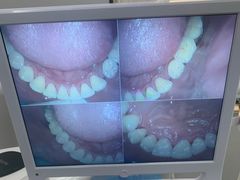

• 牙博士口腔品牌连锁(杨浦店)

• -牙博士口腔品牌连锁(杨浦店)

Honey_8448 | 22-06-16